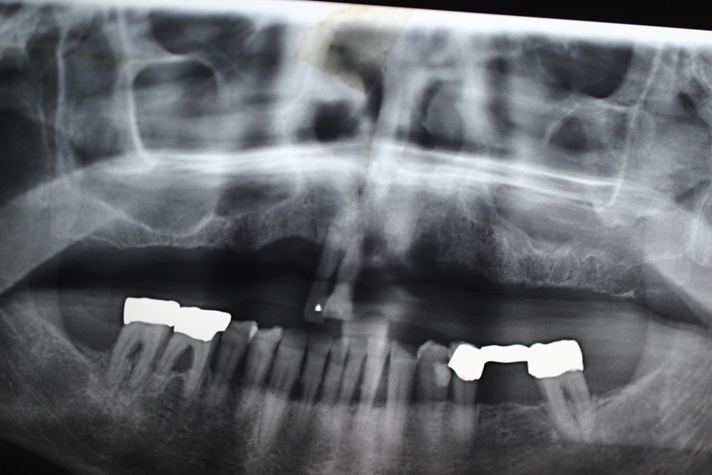

Tall and Tilted Pin Hole Immediate Loading ( TTPHIL) is a modern and most reliable technique for dental implantation. The special feature of such method is that dentist combine long and wide implants with bi-cortical support bone.

The All on 6 and All on 4 technique apply that method of implants placement.

This technique also use immediate loading so the implants are placed right after teeth extraction.

This case report show the successful All on 6 dental implantation using Alpha Dent implants.